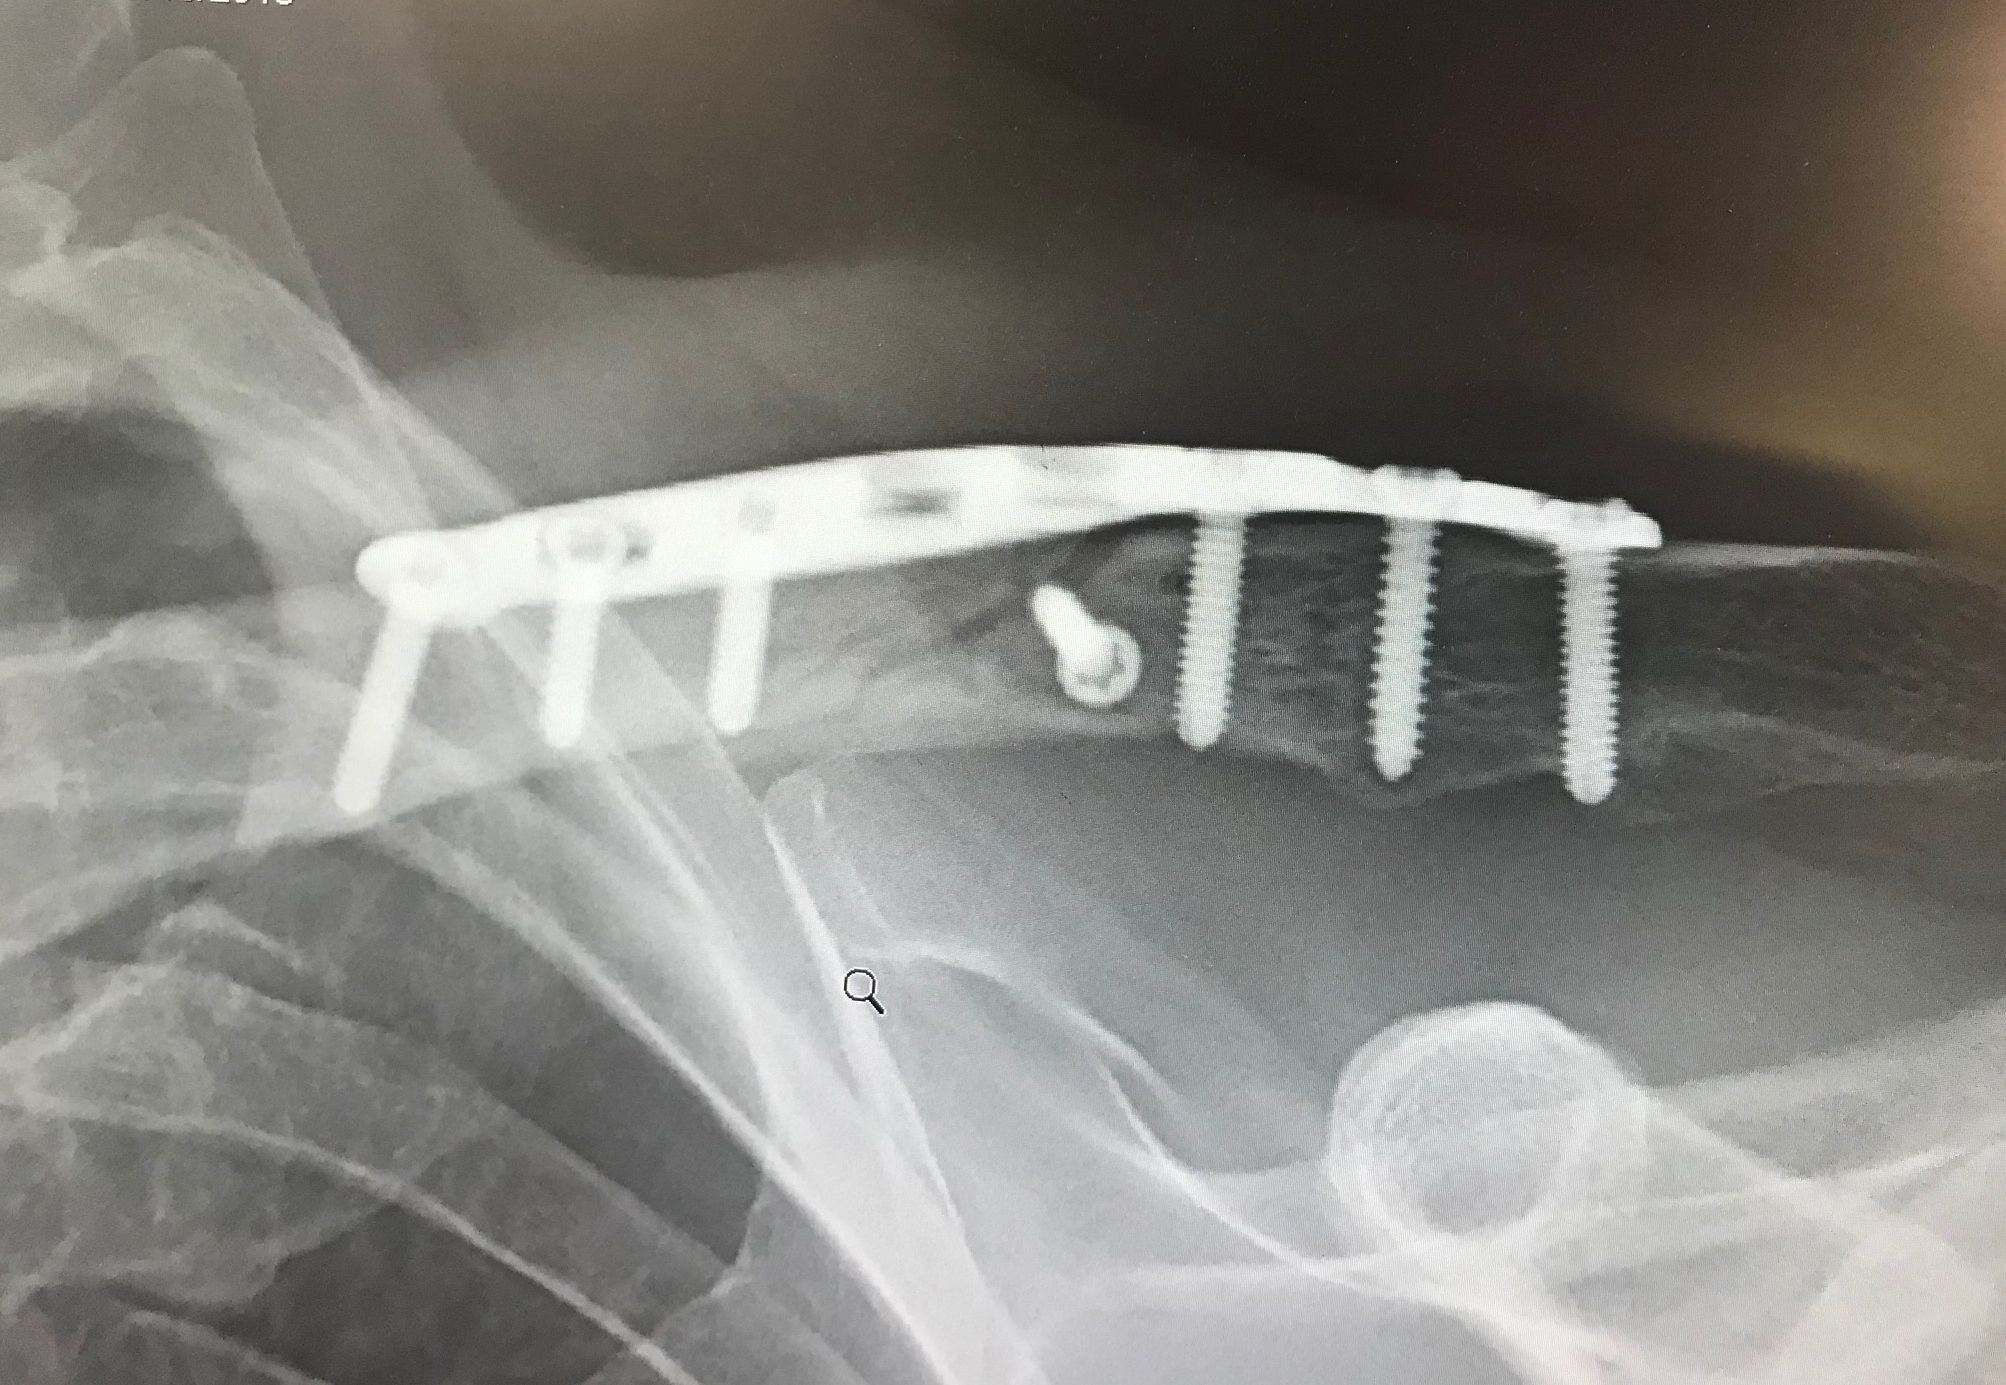

My left clavicle, however, was not so lucky. It was in pieces. As I lay on the pavement staring up at the beautiful big Montana sky, I didn’t know I had broken my clavicle, but I did have the sense that my shoulder was injured pretty badly. I knew my head was okay because I asked if my bike was alright. Turns out it mostly was, but later I would learn that I had a small puncture in my front tube, which caused my front tire to gradually lose air until it failed. Normally, you notice things like this during a ride without something so dramatic happening. It was just an unlucky thing. But I was fortunate to be riding with a group, and also fortunate that I didn’t take out any of them in my fall. They took care of me on the scene, called for help, and got me to the Emergency Room quickly.

I elected to have surgery to put the pieces of my clavicle back together, and I’m glad I did. My surgeon, who did a marvelous job, said most of the time these surgeries take 30 to 40 minutes. Mine took him 90. Yikes. Here’s the before and after: